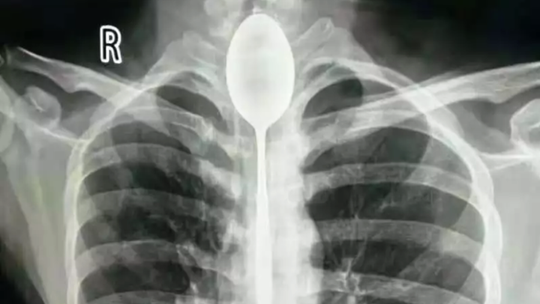

02/11/2018 03:53Muỗng dài 20 cm kẹt trong cổ họng 1 năm mới đi bác sĩ

Theo đài RT hôm 1-11, bệnh nhân nói trên – chỉ được xác định là Zhang, khoảng 20 tuổi - đã nuốt cái muỗng dài 20 cm trước mặt những người bạn của mình cách đây 1 năm.

Vào tháng 10 năm nay, anh chàng cảm thấy khó thở và đau ngực nên đi khám bác sĩ. Một bệnh viện đa khoa ở Tân Cương cho biết hình ảnh chụp X-quang cho thấy một vật thể kim loại mắc kẹt trong thực quản của Zhang. Hôm 22-10, các bác sĩ phải mất hơn 2 giờ để lấy nó ra ngoài.

Một bác sĩ chia sẻ ông rất ngạc nhiên vì chưa gặp trường hợp nào như thế này trước đây. Trong khi đó, bệnh viện nơi Zhang điều trị nói rằng anh chàng đã gặp may vì các vật thể trong thực quản hoặc dạ dày "có thể đe dọa đến tính mạng".